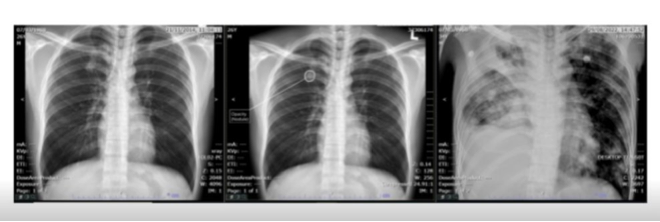

AI Can Detect Lung Nodules that Could Lead to Lung Cancer Nearly 3 Years Before Symptoms & Actual Diagnosis | Study finds https://t.co/uDxfdVZY5U via @Medical Device News Magazine